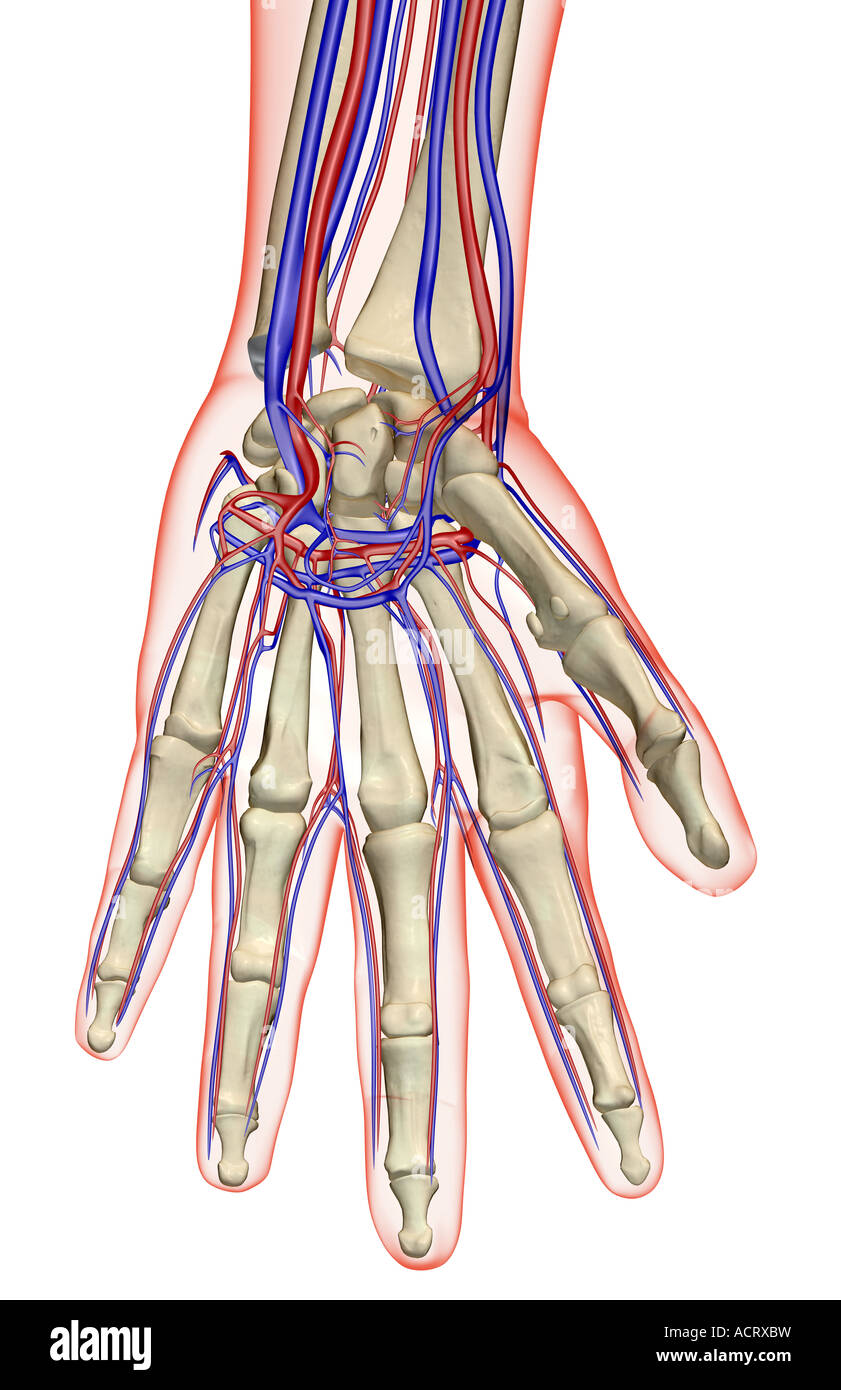

The blood supply of the hand Stock Photohttps://www.alamy.com/image-license-details/?v=1https://www.alamy.com/stock-photo-the-blood-supply-of-the-hand-13220844.html

The blood supply of the hand Stock Photohttps://www.alamy.com/image-license-details/?v=1https://www.alamy.com/stock-photo-the-blood-supply-of-the-hand-13220844.htmlRFACRXBW–The blood supply of the hand